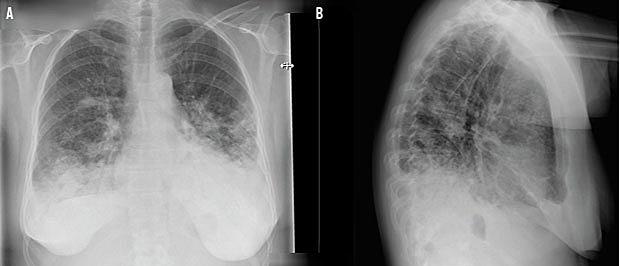

C-reaktivt protein (CRP)-koncentration på 124 mg/l, men leukocyttallet var inden for normalområdet. En røntgenundersøgelse af thorax viste bilateral pneumoni. Man påbegyndte behandling med intravenøst givet benzylpenicillin og clarithromycin samt pauserede den immunsupprimerende behandling. Over fire døgn steg CRP til 264 mg/l (Figur 1), hvorfor man udskiftede benzylpenicillin med piperacillin med tazobactam (pip/tazo), og patienten blev overflyttet til en infektionsmedicinsk afdeling. Et ekspektorat var positivt for M. pneumoniae-DNA ved PCR. Dyrkning af ekspektoratet var uden vækst og med negativ PCR for Legionella pneumophila, Chlamydophila pneumoniae, influenza A + B-virus, parainfluenzavirus, adenovirus og respiratorisk syncytialvirus. Efter behandling med pip/tazo i syv døgn og clarithromycin i ti døgn steg CRP-koncentrationen til 239 mg/l og leukocytkoncentrationen til 13,4 × 109/l (Figur 1). Klinisk var der forværring med brug af accessoriske respirationsmuskler, tiltagende tør hoste og øget iltbehov. En røntgenundersøgelse af thorax viste progression af de infiltrative forandringer. Der blev nu rejst mistanke om makrolidresistent M. pneumoniae, og clarithromycin blev udskiftet med tablet moxifloxacin. Samtidig blev der rekvireret svælgpodning til undersøgelse for M. pneumoniae-makrolidresistens, hvilket blev påvist. Blot et døgn efter påbegyndelse af moxifloxacinbehandling faldt CRP-koncentra-

Hos patienten i sygehistorien blev diagnosen M. pneumoniae stillet på baggrund af infiltrater set på en røntgenoptagelse og et ekspektorat, der var positivt for